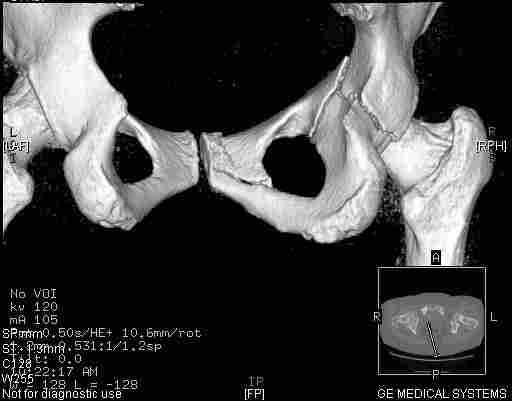

Следом 3d

Приветствую,Антон.Рункова рядом нет,но после полученных данных КТ,обсуждали совместно.Итог обсуждения-развернутый ответ дать не получится,т.к.срезы выбраны не информативные.Если ориентироваться на данные 3D,то ,ИМХО,можно лечить на вытяжении.